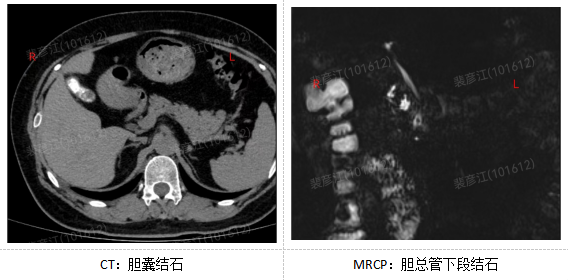

患者张先生,52岁,因反复上腹疼痛、发热、黄疸入院。经检查,明确诊断为“胆囊结石”并继发“胆总管结石”。传统治疗此类疾病通常需要进行一次创伤较大的开腹手术,患者痛苦大、恢复慢。

经过该院消化外科团队周密的术前讨论,决定采用目前国内领先的 “四孔法”腹腔镜联合手术方案。由科主任孙力指导协调,在麻醉科与手术室的密切配合下,闫景全主任医师、裴彦江副主任医师为患者施行了此次手术。